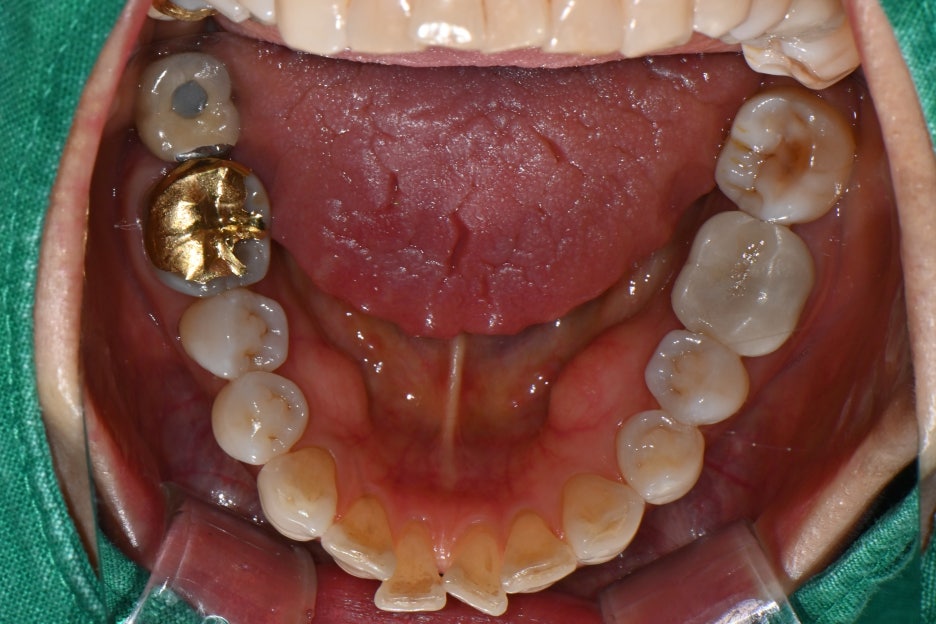

Based on the panoramic X-ray and intraoral photos,

we diagnosed the following:

The two upper left molars were fractured and missing

The surrounding alveolar bone was relatively healthy, so implant placement was possible with minimal bone grafting

Before and after treatment photos

If chewing is difficult because of a fractured tooth like in this patient,

implant treatment is possible after an accurate diagnosis regardless of age. Seoul Orbit Dental Hospital, based on university-hospital-level equipment and a system of joint care with specialists,

helps elderly patients receive implants safely.